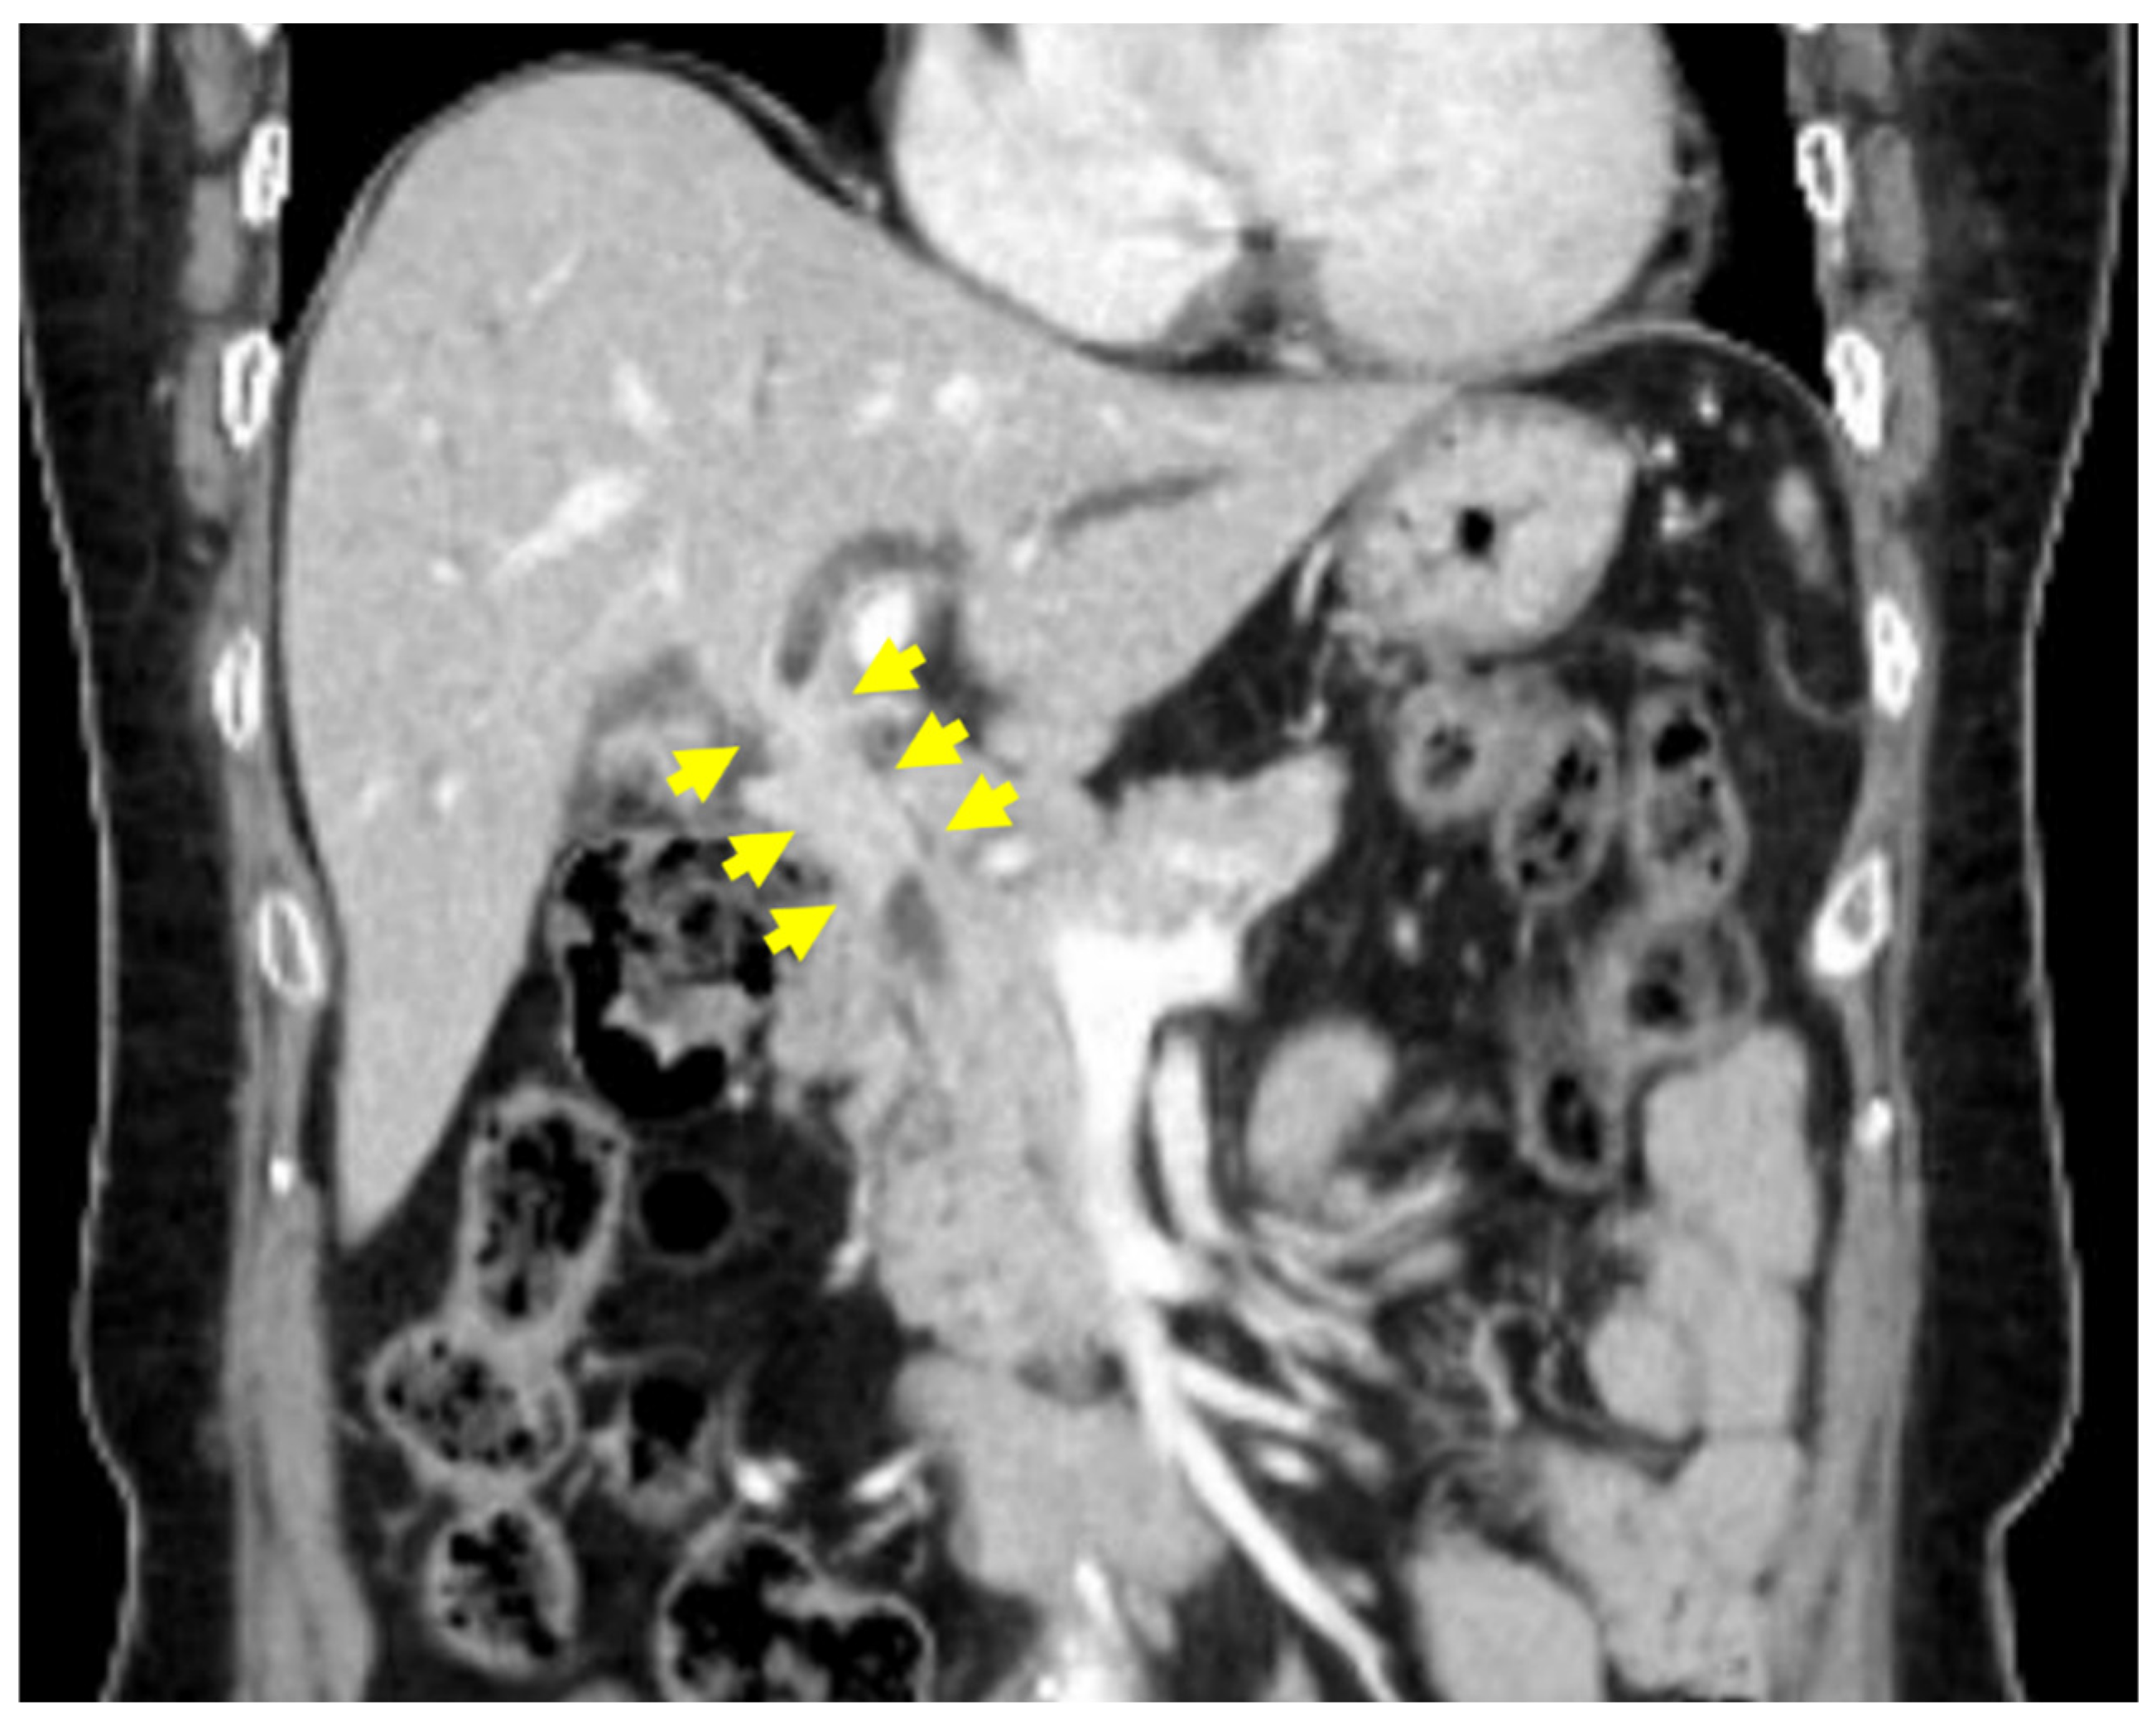

2. Case Presentation